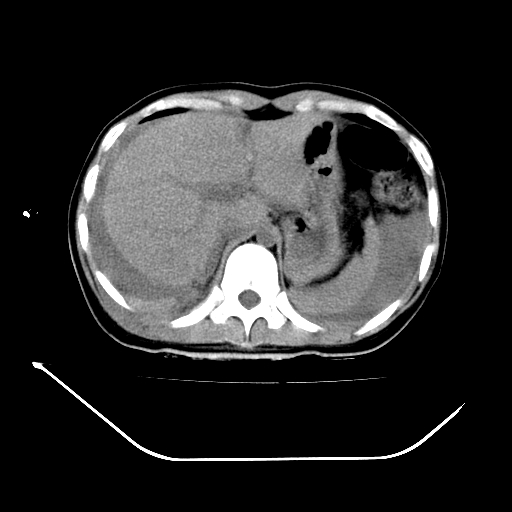

以下是引用liuyue在2008-7-19 13:02:00的发言:[br]1.肝右叶后下段及右肾挫裂伤伴腹腔积血。[br]2.右侧多发性肋骨骨折、横突骨折、右髂骨骨折伴周围软组织挫伤。[br]3.右侧腰大肌肿胀,并可见低密度影,如为气体,则肠道挫裂伤待除外。

以下是引用zhengfaming在2008-7-19 14:42:00的发言:[br]1.肝右叶后下段及右肾挫裂伤伴腹腔积血。脾脏挫裂伤待排[br]2.右侧多发性肋骨骨折、横突骨折、右髂骨骨折伴周围软组织挫伤。[br]3.右侧腰大肌肿胀,并可见低密度影,如为气体,则肠道挫裂伤待除外

以下是引用道哥在2008-7-19 16:52:00的发言:[br]肝右叶后下段及右肾挫裂伤、脾破裂伴腹腔积血。[br]2.双侧多发性肋骨骨折、横突骨折、右髂骨骨折伴周围软组织挫伤。[br]3.右侧腰大肌肿胀,并可见低密度影,如为气体,则肠道挫裂伤待除外。